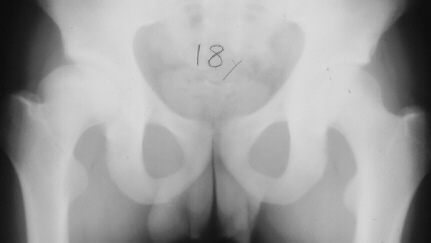

At 28 years of age, he had been having increasing pain in his right hip. He had a limp when he was tired. Positive Trendelenburg's sign was observed on the right. Internal rotation was limited to 25 degrees. All other motions were normal. X-ray showed cystic change. At the 29 years of age, he underwent bone graft of the right femoral head for degenerative cyst. At 35 years of age, only internal rotation was limited to 20 degrees. He still had pain in his hip that relates primarily to weather or to excessive walking. Only internal rotation was limited to 20 degrees. He had hip pain at the extremes of flexion and internal rotation. X-ray showed the progression of the cystic change. CT which was performed because of the question of loose bodies in the hip did not seem likely that the densities were actually in the hip joint. The antero-medial location of the cysts facing the anterior margin of the acetabulum was well depicted in CT.

28 yrs, 29 yrs, 30 yrs, 35 yrs .